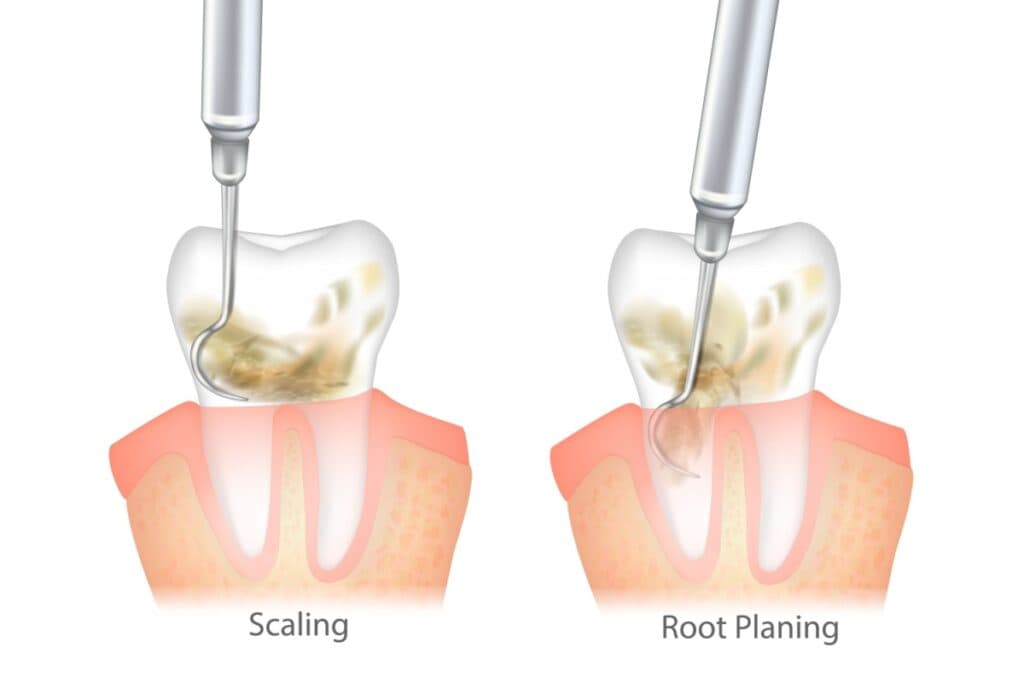

Root Planing is a deeper cleaning procedure that removes tartar buildup below your gum line, while regular cleanings focus on plaque and tartar removal from visible tooth surfaces above the gums. Your dentist may recommend root planing when you have signs of gum disease that require more thorough treatment than a standard cleaning.

Both procedures involve scaling (removing tartar), but a root planing session goes deeper to treat gum disease. Your dentist may recommend root planing when you have signs of gum disease that require more thorough treatment than a standard cleaning.

The root planing procedure goes much deeper than a regular cleaning. Your dental team works below the gum line to remove bacteria and tartar from tooth roots, areas you cannot see or clean at home.

Both regular cleanings and scaling and root planing involve removing tartar, but they work at different depths. Regular cleanings work on tooth surfaces above the gum line, the parts you see when you look in the mirror. Root planing reaches below the gum line into the pockets where gum disease bacteria hide and multiply, then smooths the tooth roots to help gums reattach.